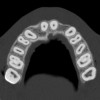

Periapical radiographs were taken to help determine the mesial-distal inclinations of the adjacent tooth roots (Figure 1). The radiographs revealed a serious issue, convergent roots for the right canine and right central, which eliminated that area as a potential implant-receptor site. The space between the left central and canine teeth was minimal, although the roots were relatively parallel. Clinical examination (manual palpation of the root eminences superiorly to the vestibule on the right side) confirmed the root convergence (Figure 2A). The flat, wide zone of the keratinized tissue and lack of interdental papilla was evident for the missing right lateral incisor. There was a marked difference in clinical appearance for the left lateral, which could impact the eventual plan of treatment (Figure 2B). Other significant clinical findings included bilateral facial bone concavities, which existed as a result of the congenitally missing tooth roots. As a diagnostic cue to the underlying bone topography, it is important to follow the demarcation between attached and unattached gingival tissue, and note the crestal width of the available keratinized tissue (Figure 2C).

Figure 1  Pretreatment radiographs revealed convergent roots for the right canine and right central.

Figure 1